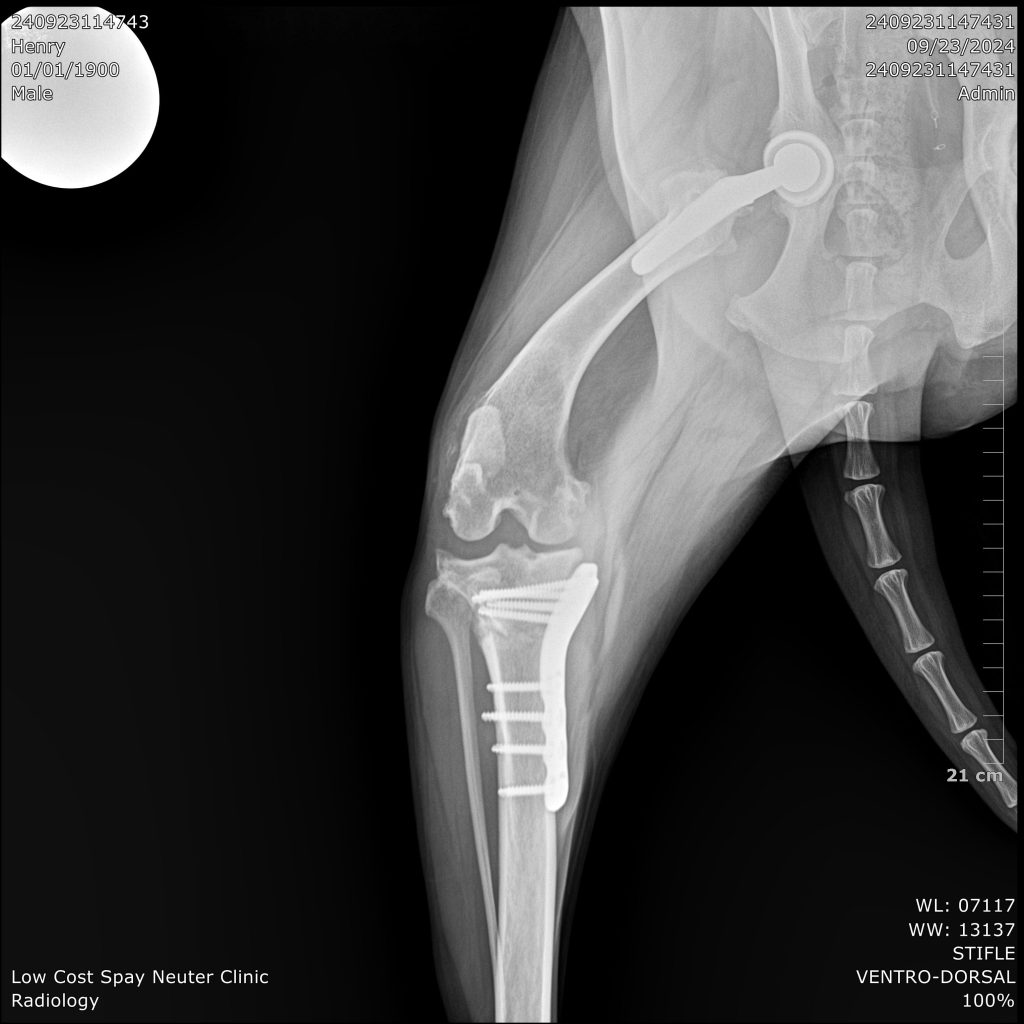

Cranial Cruciate Ligament; (CCL) is one of the most important stabilizers of the knee. It prevents hyperextension, limits internal rotation, and prevents the tibia (shin bone) from sliding forward each time the leg bears weight. When the CCL is damaged, the result is an unstable knee. This instability results in pain and inflammation. Over time, debilitating arthritis develops. Rupture of the cranial cruciate ligament (CCL) of the stifle joint (=knee) is one of the most common orthopedic injury in dogs. It may happen acutely as the result of a true traumatic injury or slow deterioration of the ligament as a dog ages.

TPLO (Tibial Plateau Leveling Osteotomy) surgery stabilizes a dog’s knee joint by altering the angle of the tibial plateau (the top of the shinbone), effectively neutralizing the forces that cause instability when the CCL is damaged. Instead of attempting to repair the torn ligament, TPLO stabilizes the joint by changing the way the femur (thigh bone) and tibia interact during weight-bearing, eliminating the need for a functional CCL.

Price Range $1,200-$3,000